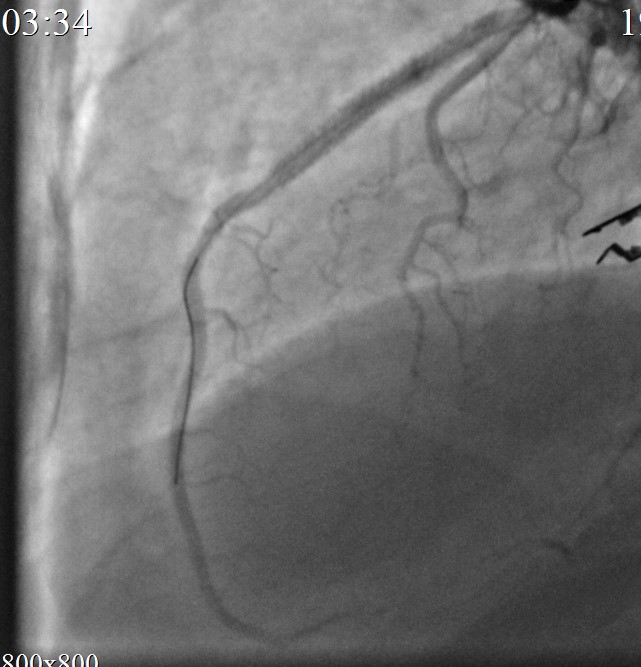

Контрольная КАГ: успешное «пломбирование» разрыва. Кровоток по ПМЖВ TIMI III, в динамике без экстравазации.

Объективно: состояние пациента без ухудшения. Гемодинамика самостоятельная, АД 130/78 мм рт ст PS 80 в мин ЧДД 16 в мин. Жалоб не предъявляет.